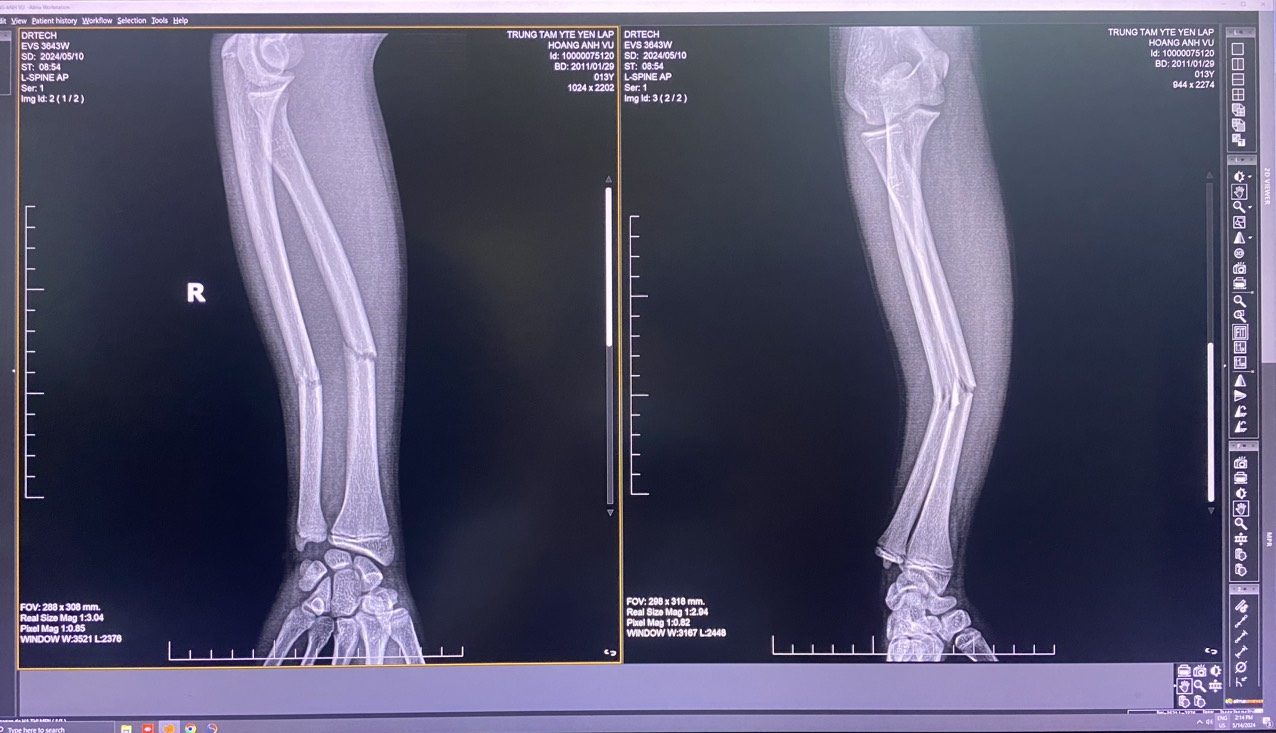

Sau khi thực hiện kỹ thuật, kết quả chụp Xquang cho thấy hình ảnh xương về đúng vị trí giải phẫu 99%, đầu chi ấm hồng, cảm giác vận động được, bột chắc. Người bệnh và gia đình được hướng dẫn theo dõi, chăm sóc tại nhà và lịch tái khám.

Sau khi thực hiện kỹ thuật, kết quả chụp Xquang cho thấy hình ảnh xương về đúng vị trí giải phẫu 99%